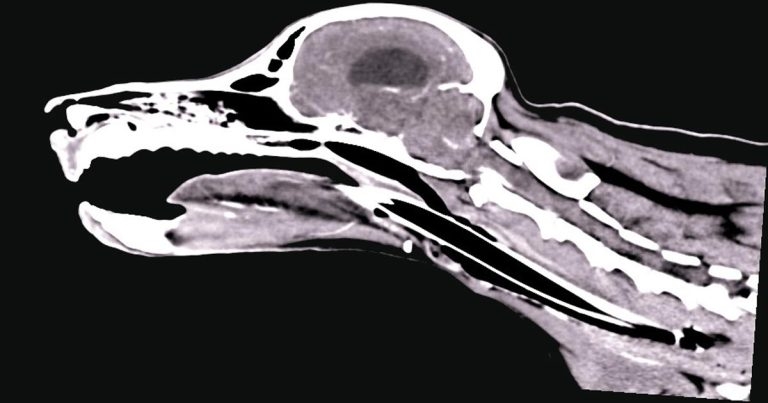

Figure 2. A sagittal CT image showing a typical appearance of a nasopharyngeal stenosis (note the small band of tissue crossing the nasopharynx).

Nasopharyngeal stenosis (NPS; Figure 2) is a pathological narrowing within the nasopharynx caudal to the choanal. Clinical signs associated with this include both inspiratory and expiratory stertor, along with recurrent nasal discharge/infection.

While NPS can be a congenital abnormality, the majority of cases occur following aspiration rhinitis as a complication of general anaesthesia. Surgical options for NPS are associated with relatively high recurrence rates, so minimally invasive fluoroscopic assisted procedures are regarded as the gold standard.

Options for NPS include balloon dilation or placement of a stent. Balloon dilation and stent placement should only be considered after a contrast CT scan of the area is performed to allow accurate measuring and precise identification of the stenosis.

The stenosis is most commonly located at the junction of the hard and soft palate,but can occur both rostral and caudal to this.

For very thin lesions (less than 0.5cm), multiple balloon dilations alone may be successful. However, for lesions more than 0.5cm, recurrent lesions or complete stenosis, balloon dilation alone is unlikely to be successful and placement of a nasopharyngeal stent should be recommended.